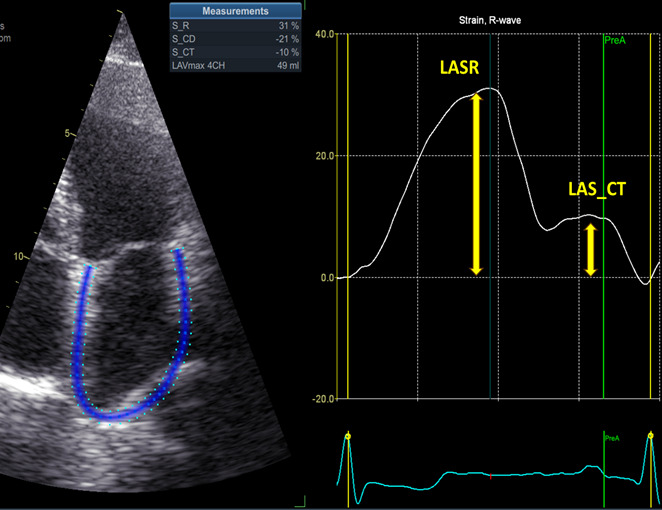

Results: Patients who had inflammation showed higher values for the CHA2DS2-VASc and HAS-BLED scores (P= 0.0132 for CHA2DS2-VASc and P= 0.0024 for HAS-BLED). Also, it was observed that patients with associated inflammation exhibited an increase in both the volume and the area of the left atrium. Patients with hypertension had a higher prevalence of inflammation, with heart failure and with ischemic heart disease. It is worth noting that patients with atrial fibrillation and increased inflammatory status exhibited higher rates of stroke (22.75% vs 10.71% in patients without inflammation, odds ratio = 2.455, 95% confidence interval 1.161 to 5.425, p = 0.0253).